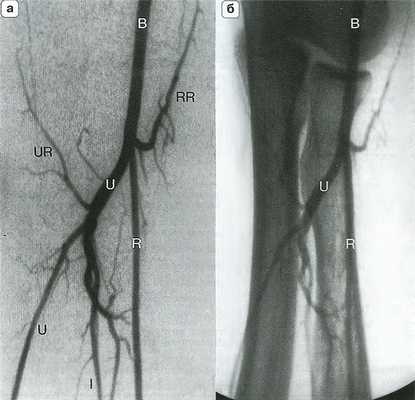

Рис. 14.4. Артериальная анатомия (а) и костные ориентиры (б) локтевого сустава. Плечевая артерия (В) делится на уровне локтевого сустава на лучевую (R) и локтевую (U) артерии. Межкостная артерия (I) является ветвью локтевой артерии, которая в некоторых случаях продолжается на кисть. RR - лучевая возвратная артерия; UR - локтевая возвратная артерия.